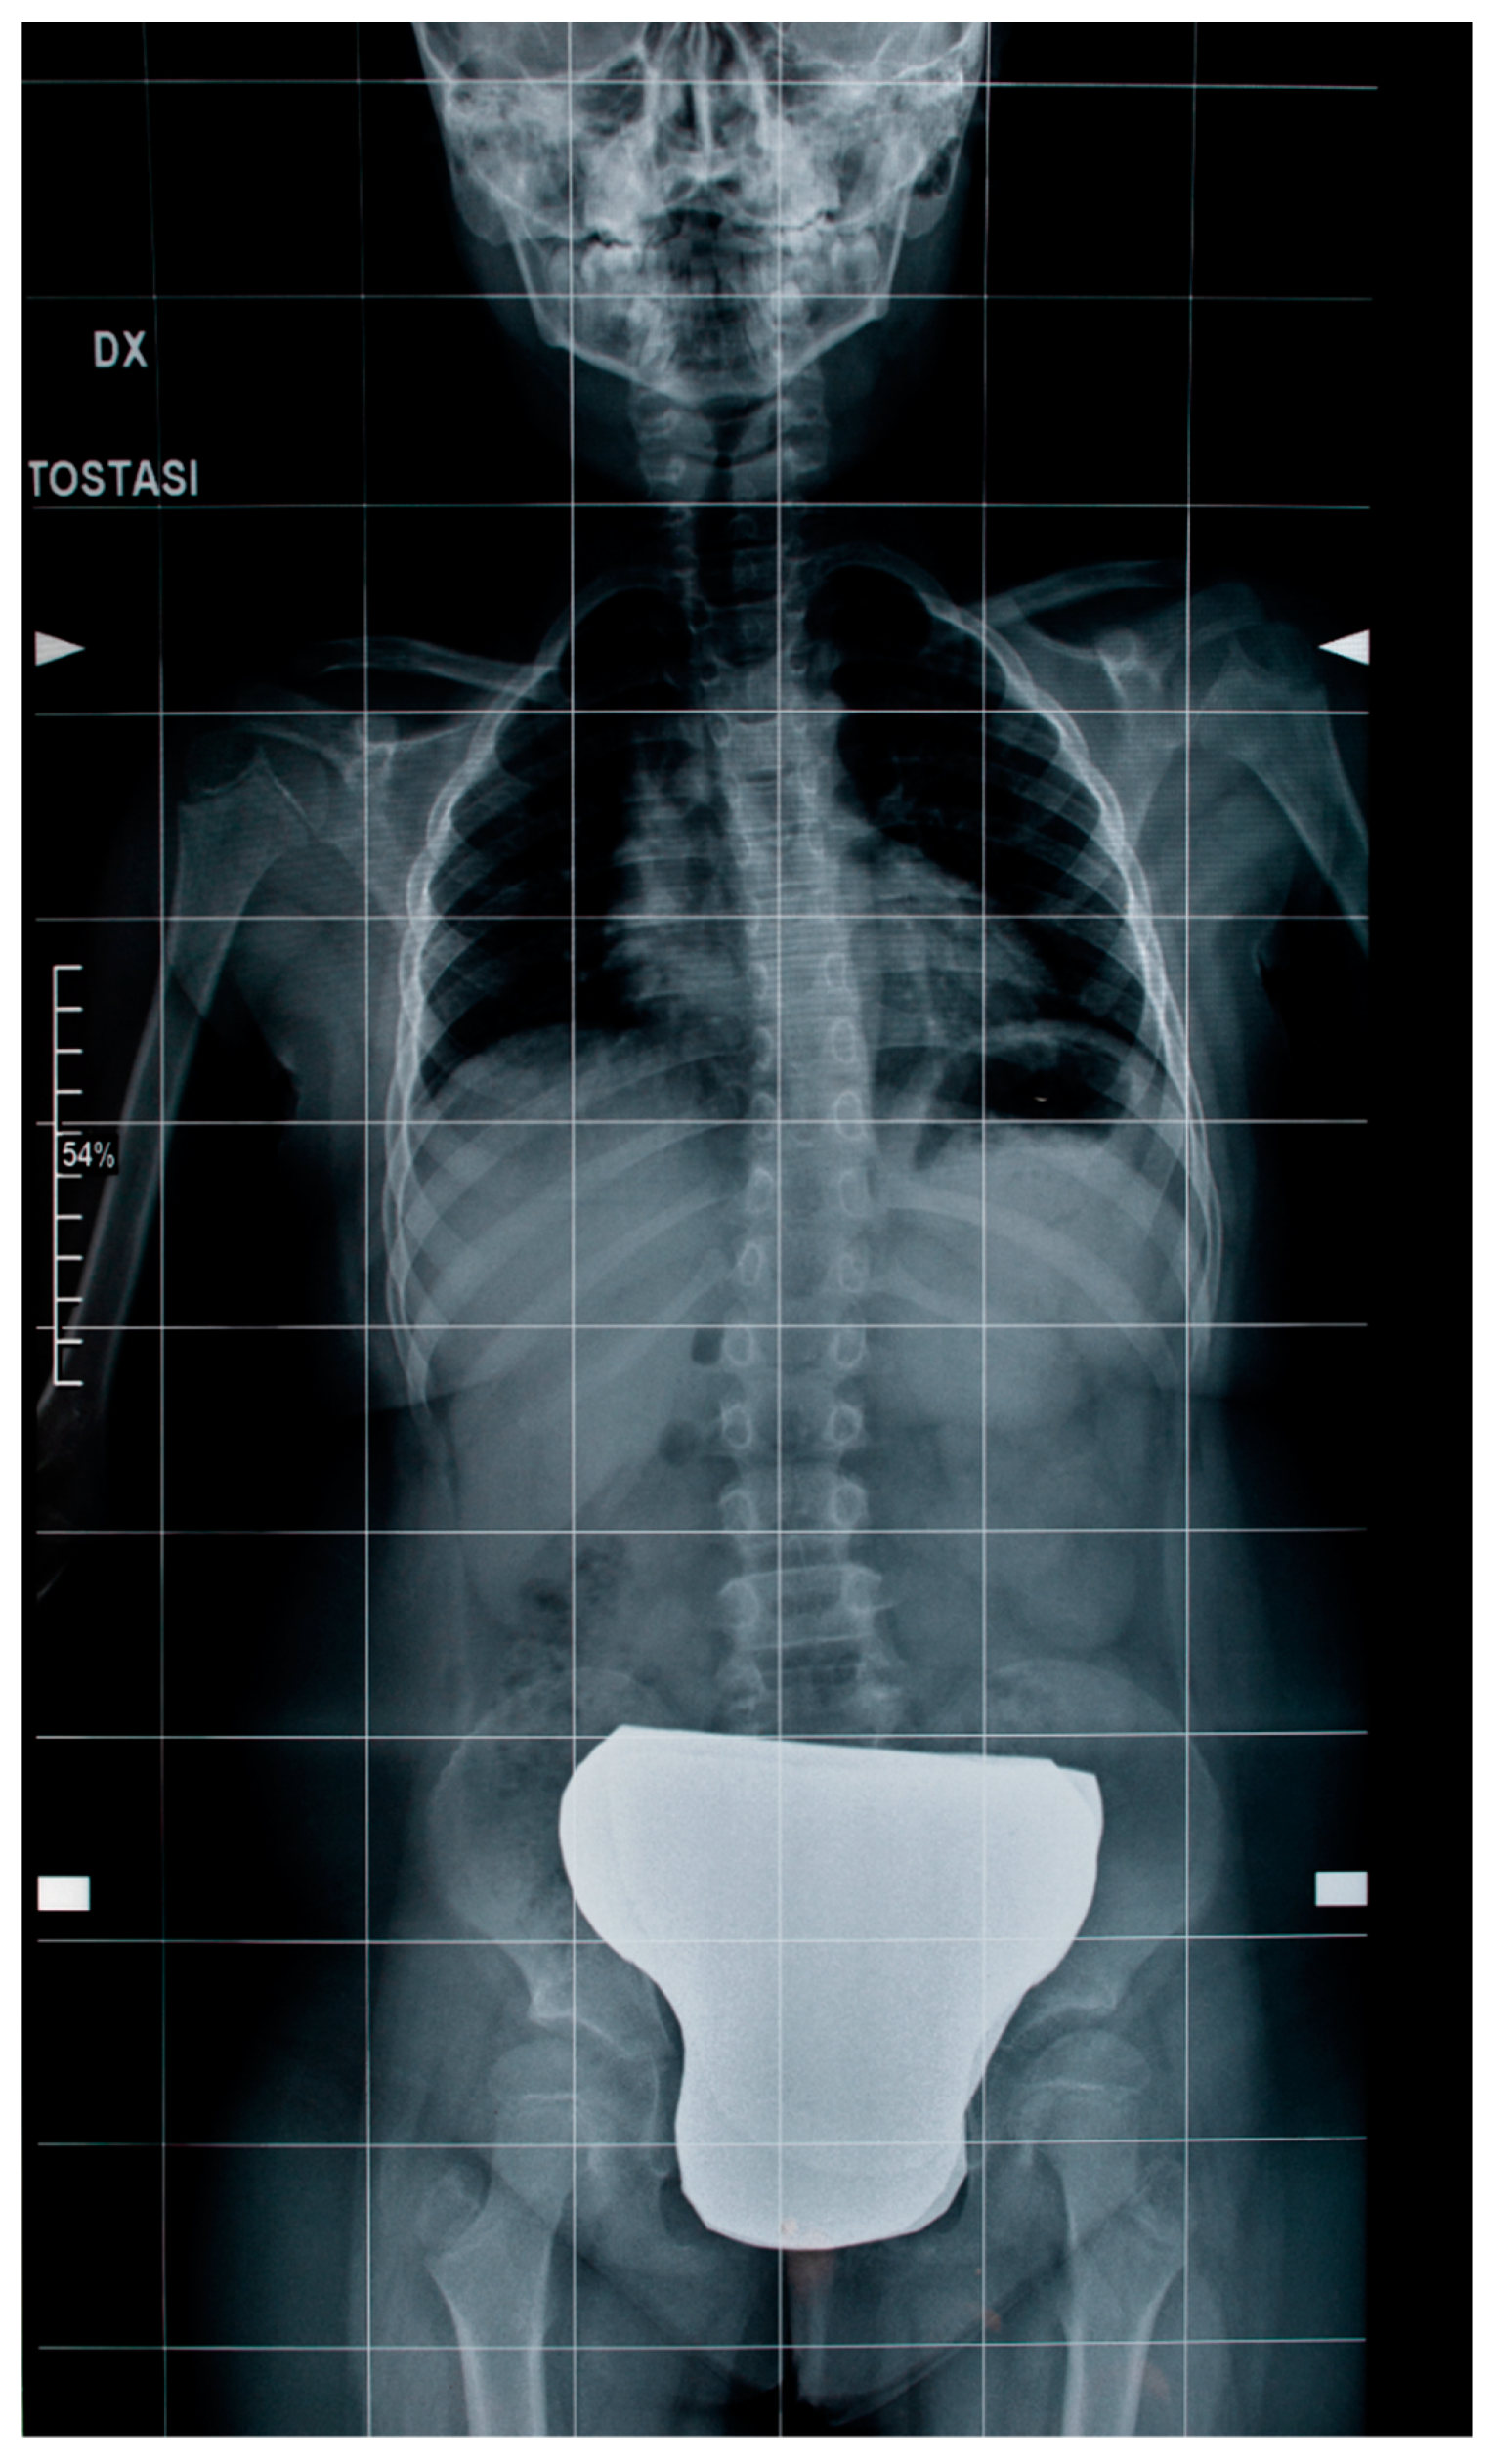

Orthopedic examination and standard X-rays of the spine revealed a scoliotic attitude or “pseudo scoliosis” of the dorsal–lumbar spine associated with unlevel shoulders and left thoracic hump with Risser Grade 0. No lumbar salience or vertebral rotation signs were found (Figure 6). Unfortunately, we have no data on how scoliosis has changed over time to determine its progression because of the family’s lack of cooperation in carrying out the periodic clinical and instrumental investigations that this case required.

Figure 6. Standard X-rays of the spine revealed a scoliotic attitude of the dorsal–lumbar spine.